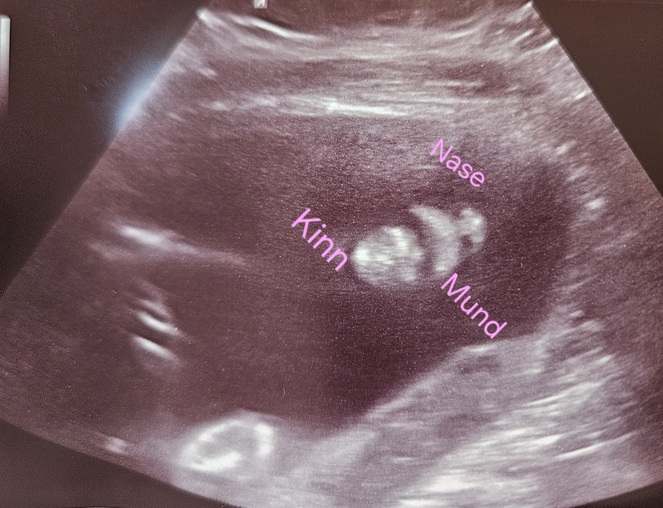

Der nächste Ultraschall steht an :) - Tagebücher aus der Schwangerschaft von Marie aus bei Heidelberg